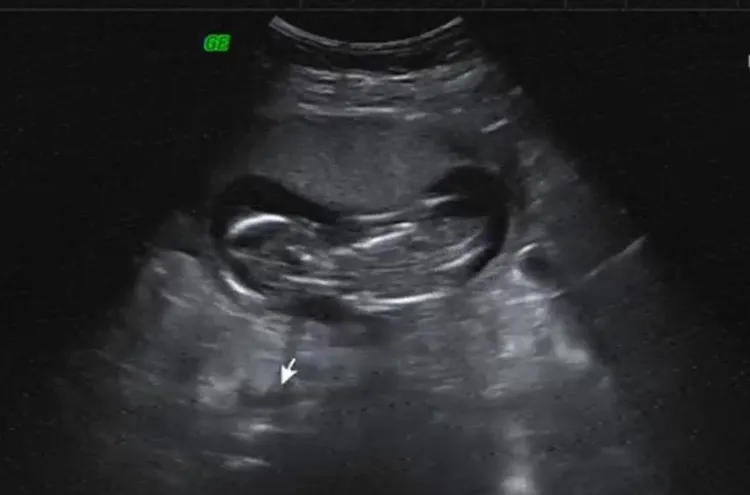

葉家妤秀胎兒超音波照。民視提供